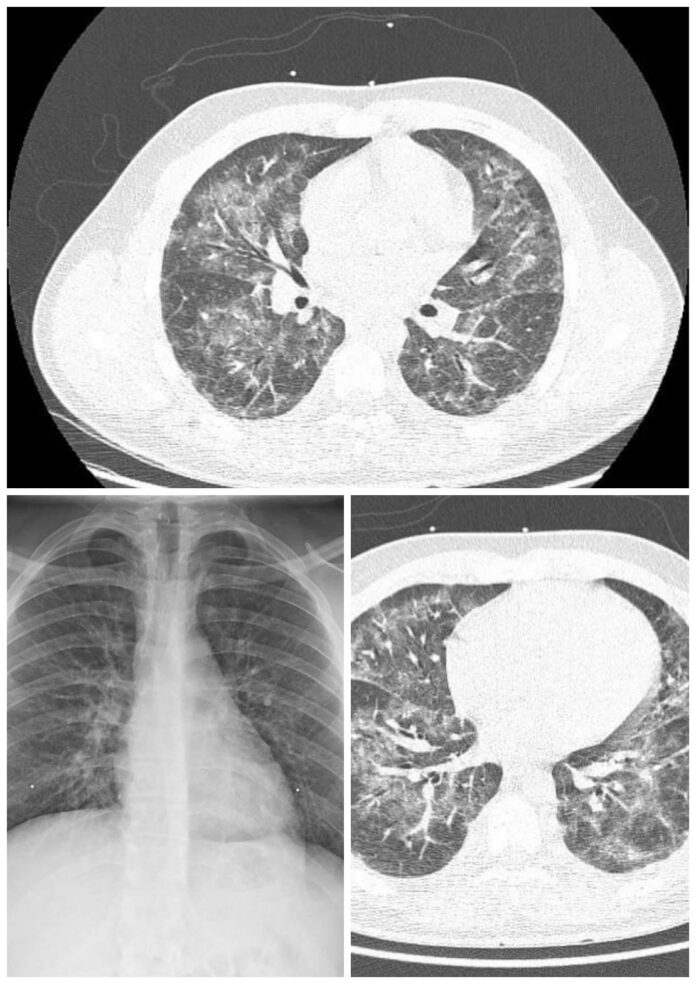

Ăștia sunt plămânii unui tip în vârstă de 20 de ani, care fumează țigară electronică. A ajuns la spital cu dureri și cu senzația de sufocare.

Boala este una relativ nouă și se numește EVALI, adică E-cigarette or Vaping Product, Use Associated Lung Injury. Adică leziuni pulmonare provocate de substanțele din țigările electronice și din lichidele pentru vaping. Se și moare din cauza lor.

Deci când vă mai spune cineva de la IQOS sau Glo că țigările electronice sunt sănătoase, să-i arătați pozele astea și să-i spuneți să plimbe ursul. La fel și când vedeți firme sau site-uri unde scrie “fumează sănătos”.

PS: cele mai vehemente reacții la postarea asta sunt de la fumătorii care încearcă să se convingă că e bine să fumezi sau de la vânzătorii de țigări electronice. Realitatea e fix asta din imagini.